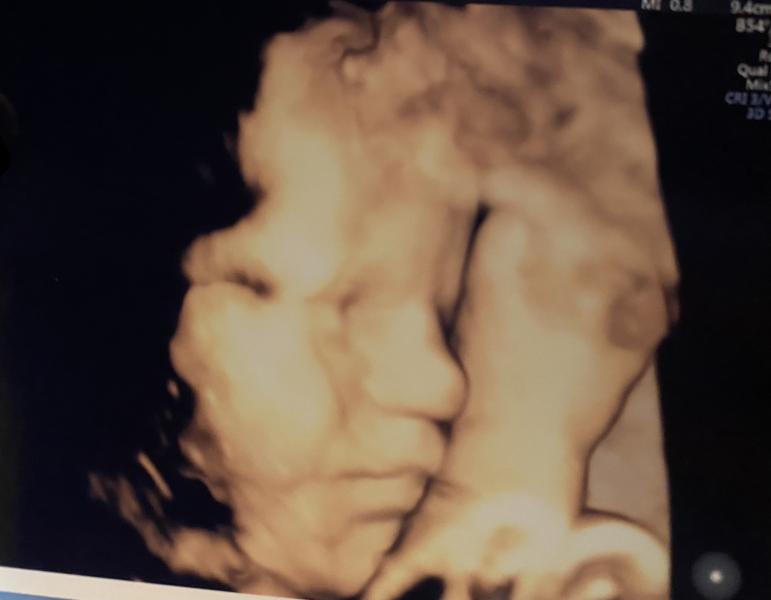

P.S. Третий скрининг прошли, к счастью, все соответствует срокам. Чуда не случилось, ДМПП не затянулся, но и не увеличился, что уже хорошо.